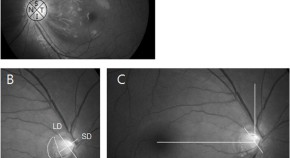

Ophthalmic findings are common features of neurodegenerative disorders, and have emerged as potentially useful biomarkers of disease progression in several conditions. Kersten et al. describe the various afferent visual system and other ophthalmic features of inherited neurodegenerative disorders, focusing on the expanding role of optical coherence tomography in diagnostic imaging of the retina and optic nerve head. They also discuss the ophthalmic manifestations and treatment implications of mitochondrial dysfunction—a feature of many inherited neurodegenerative diseases.